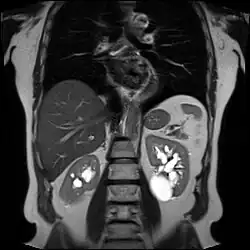

| Photo of liver and pancreas showing multiple cysts in the latter in a patient with renal–hepatic–pancreatic dysplasia | |

Through observation of fetuses that had passed away, it was determined that this syndrome has key representative external and microscopic appearances that can help diagnose the condition. The kidneys in many cases, appear to be enlarged, with cysts distributed throughout the tissue. Molecularly, many basic nephron structures, the part of the kidney that produces urine,[7] are not identifiable or present. The appearance of the liver is often firm, with many cysts throughout. Microscopically, irregular bile duct development is detected, further restricted by thick scar tissue. The pancreas typically consisted of disorganized tissue and ducts that were dilated and not thoroughly developed. It was occasionally covered in cysts, with thick scar tissue throughout the organ.[8]